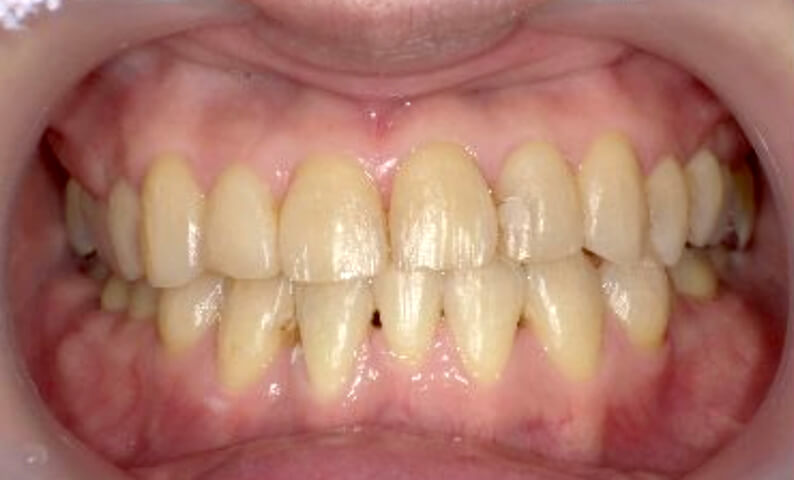

症例_003 上下顎の部分矯正

治療期間:12ヶ月金額:54万円+税男性八重歯前歯のガタガタ

| Before | After |

|---|---|

|